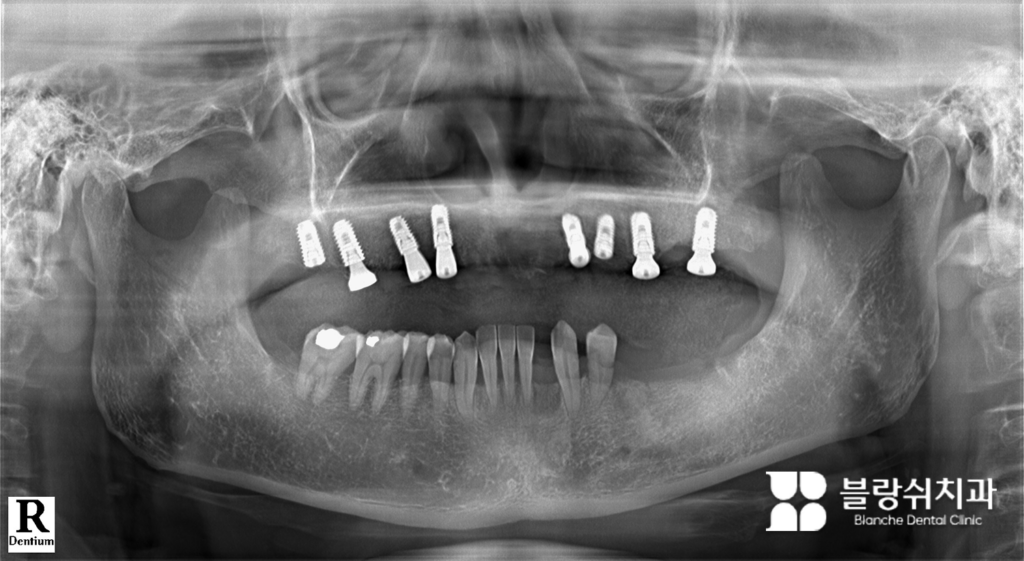

(2) 전체 임플란트 심기

윗니를 모두 뺀 뒤 임플란트 8개를 심었습니다. 개수보다 뼈가 가장 좋은 위치에 정확히 심는 게 핵심입니다. 원래 치아가 기울어져 있어도 그 각도를 그대로 따라 심지 않습니다. 정상적으로 씹는 범위에 맞춰 각도와 위치를 다시 설계합니다. 전체임플란트는 단순히 심는 게 아니라 씹는 균형을 다시 맞추는 과정입니다.

(6) 전체 임플란트 최종 완성

적응 과정을 충분히 거친 뒤, 최종 인공 치아를 달아서 윗니 전체임플란트를 완성했습니다. 정기 검진과 관리만 잘하면 오래 안정적으로 쓸 수 있습니다. 실제로 씹기 힘들어서 죽이나 미음만 먹던 환자가 치료 후 일반 식사를 하면서 소화 기능과 체력, 사회 활동까지 좋아지는 경우가 많습니다. 보기 좋게 변한 것도 자신감 회복에 큰 영향을 줍니다.